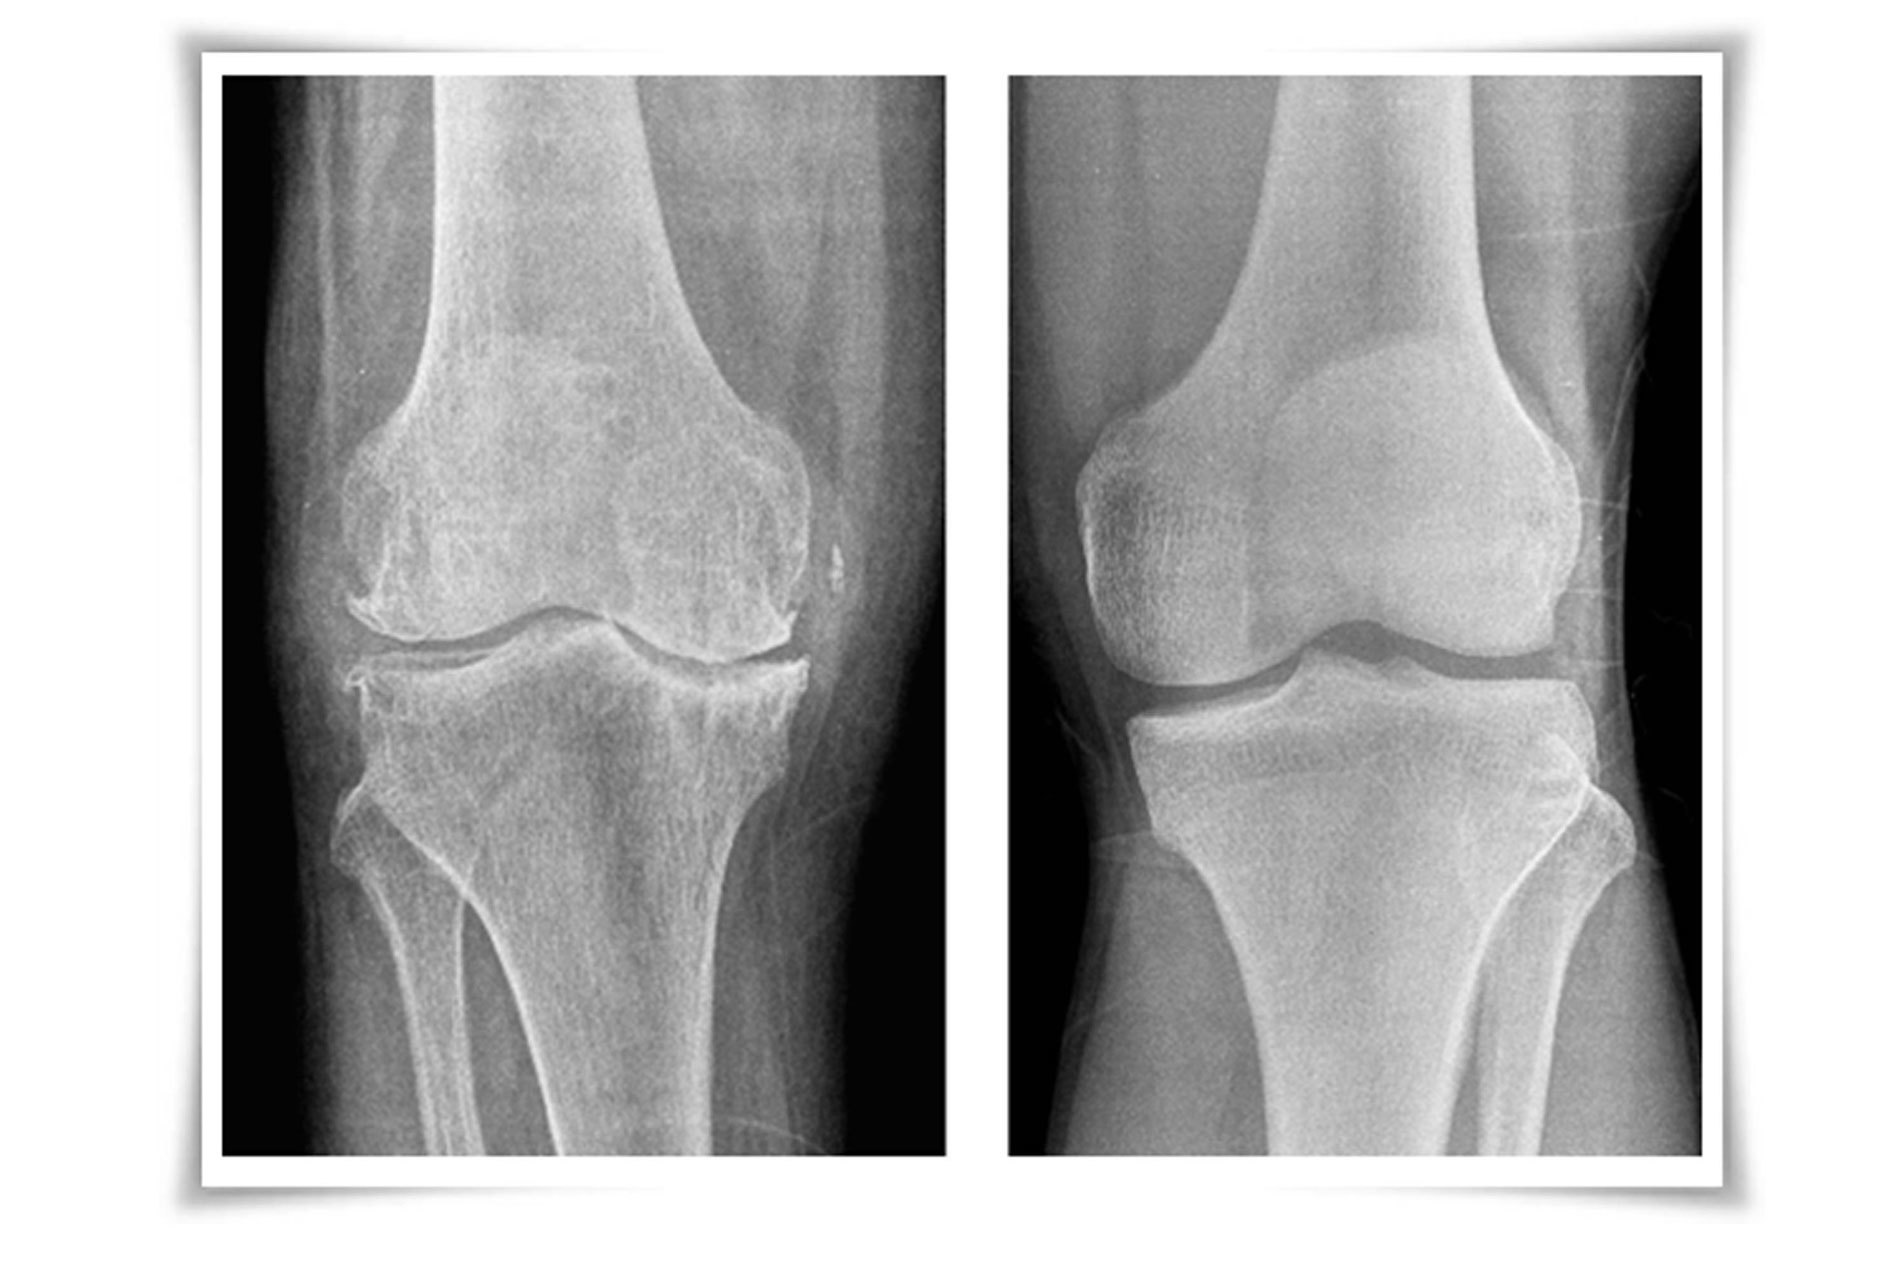

60세 이상의 환자에서  흔히 발생하는 퇴행성 질환으로 서있거나 걷는 등의 체중부하 운동에 의하여 악화되고 휴식 시 완화되는 양상을 보입니다. 아침에 일어나면 경직을 느끼고 활동하면서 풀리기도 합니다.

운동범위가 감소하고 관절의 부종, 마찰음이 관찰되기도 합니다.

주사치료 시 사용되는 연골주사는 관절의 윤활작용과 점성을 회복시켜 통증을 줄이고 기능을 향상 시킵니다.

스테로이드 주사는 염증 감소 효과는 뛰어나지만 일시적이며 장기간 사용시 오히려 관절염의 악화를 불러옵니다.

주사와 보전적 치료에도 증상이 심할 경우 인공관절치환술을 고려합니다.